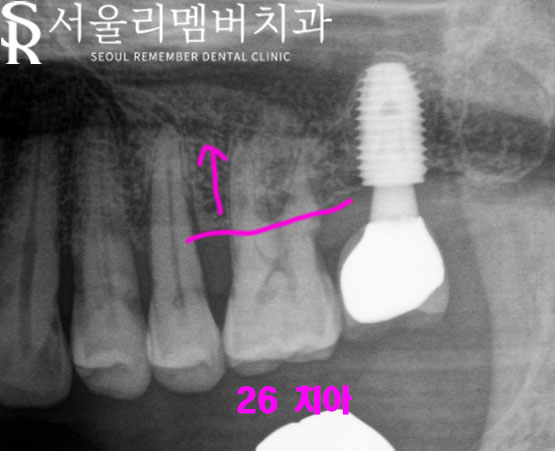

26번 치아는 잇몸 퇴축이

이루어져 뿌리가 나뉘는

분지구가 밖으로 드러나

그곳에 치석이 쌓여

우식으로 진행되어 있었고